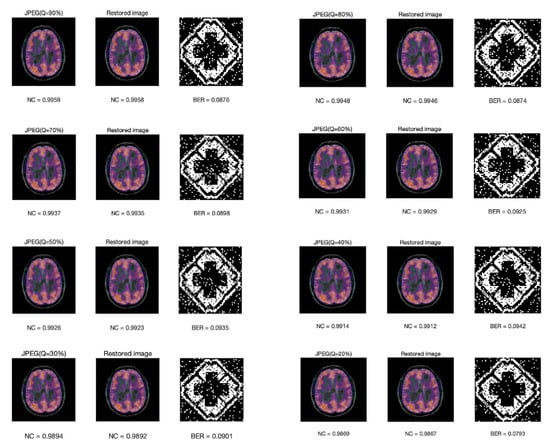

Figure 13 shows the NC value of the compressed image, the recovered image, the extracted watermark image, and its bit error rate under different JPEG compression factors. Note that the scheme is robust to JPEG compression. It is surprising to see that the worst quality JPEG at 20% yielded the smallest BER. In fact, it is not that 20% compression yields better results, but that they all keep in the same level at about 0.08–0.09. The BER of JPEG at 20% is 0.793 in our experiment, which is closely related to the images we use. Whether their BER can be kept at the same level is related to the embedding scheme. In our research, the embedded watermark is represented by the coefficient relationship between each band after DWT transformation and the relationship between one block and the next. After JEPG compression, the image quality is declined. Take the NC value for example, NC is smaller after compression, but there is not much loss of the relationship between block and sub-band, so the watermark can still be extracted precisely. However, for attacks that destroy the relationship between block and sub-band, such as Gaussian noise, the BER is relatively high, which is about 0.3.

Figure 13.

The NC value of the compressed image, the NC value of the recovered image, the extracted watermark image, and its BER under different JPEG compression factors.